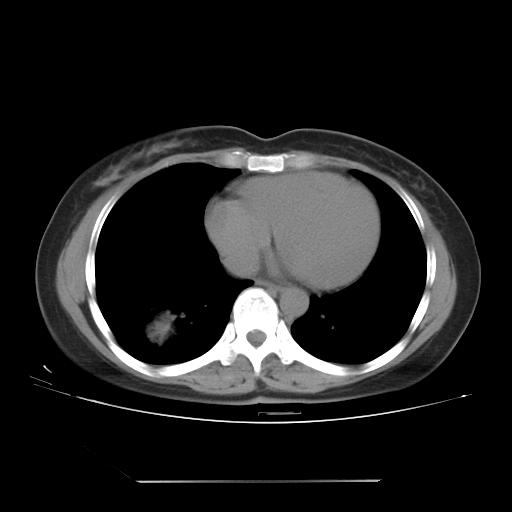

女 46岁,咳嗽咳血10月

【linyiming】右肺下叶见类圆形软组织影,边缘欠规整,略分叶状。考虑炎症假瘤可能?

【刚起步】只有想不到的,没有长不到的。实性结节,强化明显,病人咳血,肺癌不能除外。

【aosangwa】肺癌的主要特征是:毛刺征、分叶征及胸膜凹陷征,此病例位于右肺下叶距胸膜很近,但没有胸膜凹陷征,其周围像示渗出性病变,病灶在两窗上没有大小没有发生大小改变。

考虑其良性肿瘤,炎性假瘤可能性大,其主要鉴别是:结核球、周围型肺癌、血管瘤

病理诊断类癌(周围型)。